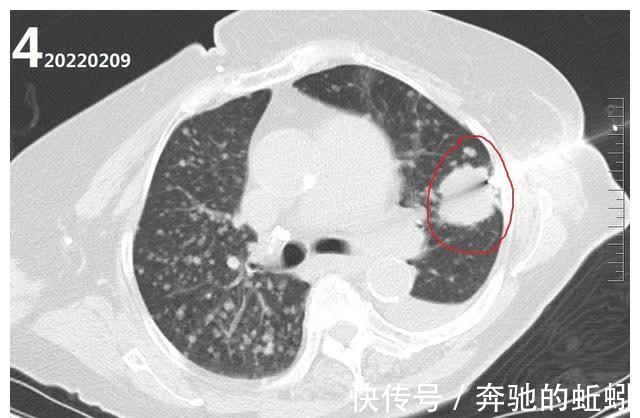

然后直到2022年2月9号才入院继续针对肺部病变进行针对性诊治。入院查胸部CT图4所示,肺部病灶较2021-12-9数目明显增多,安排了左肺病灶穿刺活检及胸壁肿物穿刺活检。

活检结果肺内病灶考虑肺腺癌、胸壁肿物考虑转移性肿瘤。